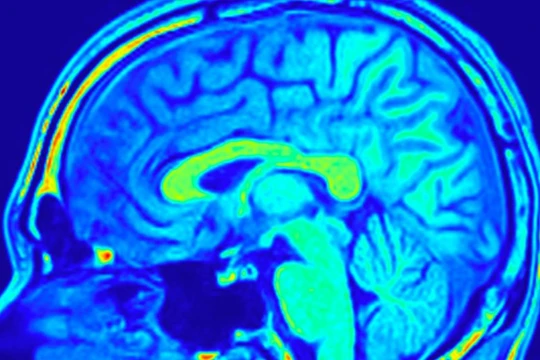

Một bước đột phá quan trọng trong chẩn đoán ung thư vừa được công bố: AI có thể phát hiện các khối u não nhỏ đến mức thường bị bỏ qua bởi chụp cộng hưởng từ (MRI).